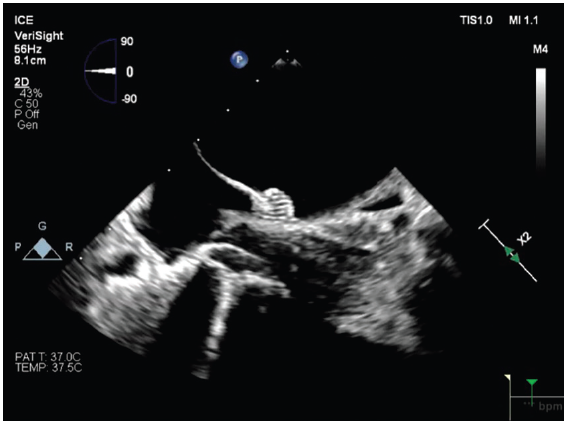

We began using the VeriSight Pro 3D ICE Catheter (Philips) to support our LAAO procedures. Incorporating 3D ICE streamlined the workflow and enhanced procedural safety, but what stood out most was the clarity of the imaging. The high-definition views provided by the VeriSight Pro allowed me to visualize the LAA, the occlusion device, and surrounding anatomical structures with exceptional detail.

There are several additional advantages to this catheter. Because we are using these catheters in the LA, there was concern about whether manipulation of the ICE catheter in the LA could increase risk of perforation; however, the VeriSight Pro’s atraumatic tip offers an added margin of safety, reducing the risk of perforation even with necessary manipulation. Its 3D technology enables multiplanar imaging with minimal catheter movement, allowing us to obtain multiple essential views while keeping the catheter largely in a single position. This significantly simplifies performing LAAO with 3D ICE. The ability to generate 3D reconstructions and use 3D color Doppler flow further enhances our understanding of anatomical relationships and helps confirm the absence of peri-device leaks.

Ultimately, my choice of catheter is driven by the specific needs of the procedure we are performing. In my lab, the VeriSight Pro 3D ICE Catheter has been particularly useful to support LAAO procedures. The ability to obtain multiple viewing angles, digitally rotate images, and achieve multiplanar visualization with minimal catheter movement has simplified my ability to obtain multiple imaging views to guide LAAO, and has become my standard approach for these procedures.

I have also found significant benefit in placing the VeriSight Single Plane Steerable ICE Catheter into the LA via transseptal access. This approach provides remarkable views of the pulmonary veins (PVs), particularly the right-sided veins, which can be challenging to visualize from the right atrium (RA). The perspective from within the LA gives us a much clearer understanding of catheter positioning, ensuring adequate contact and confirming that we are delivering lesions precisely where we intend around the PV antra.

By steering the ICE catheter into the LA, we gain a clearer appreciation of PV anatomy and orientation relative to the LA, and how our catheters lay in relation to the PV antra. Detailed ICE imaging from the LA allows us to see these relationships far better than before, ensuring that our ablation catheter is in contact with the intended areas and that we are truly treating the tissue we aim to ablate.